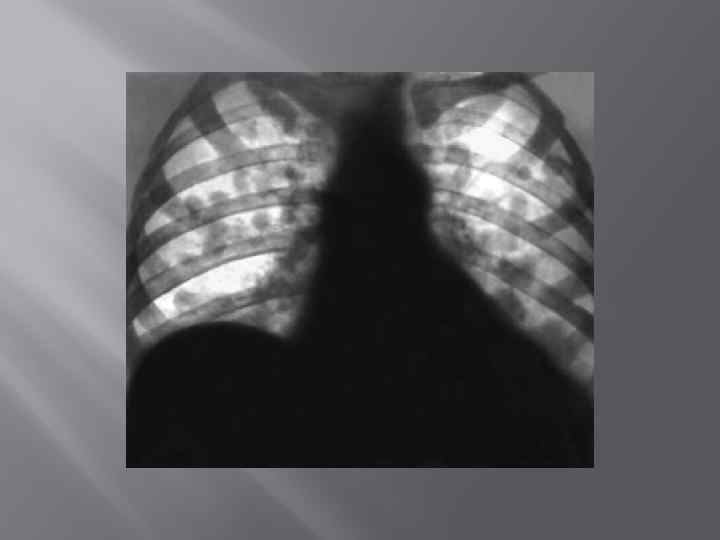

Боковая рентгенограмма больного с левосторонней пневмонией, вызванной Mycoplasma pneumoniae